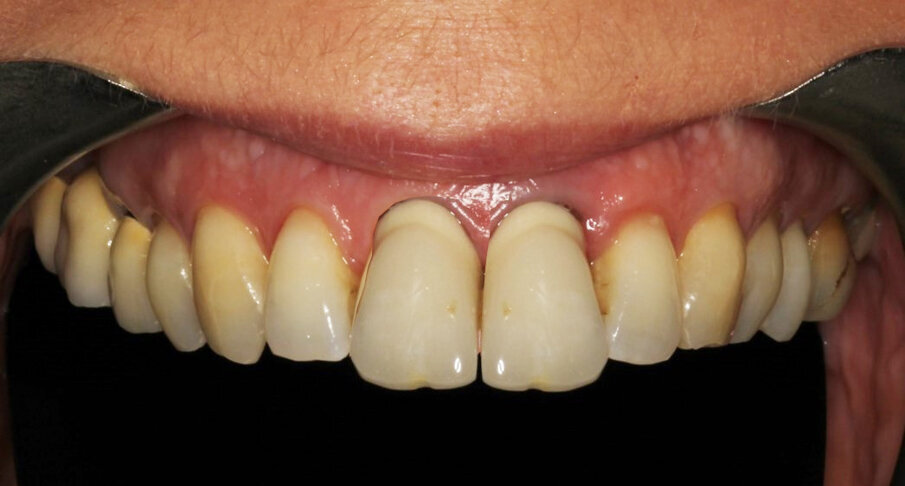

Definitive crown

The author strongly prefers screw-retained devices. Owing to the angulation of the implant, it was necessary to relocate the screw access hole. In CAD, the design for a cobalt-chromium support that copied the gingival profile of the temporary was prepared, and the screw access was brought to the palatal aspect (Fig. 37). The file was sent to the Arc solutions milling centre in Helsingborg in Sweden. High-quality material and CAM production guarantee an excellent outcome in terms of connection and smooth surfaces (Figs. 38–40). The technician layered feldspathic ceramics to obtain the final anatomy and texture. The patient was totally satisfied with the result and did not wish for intervention for the maxillary right central incisor. Minor gingival asymmetries, though evident at high magnification in photography, are not really disturbing when viewed at social distance if all other parameters, like colour, incisal edge, tooth texture, correct proportion of the incisal two-thirds of the tooth and transitions, are respected (Figs. 41–43).